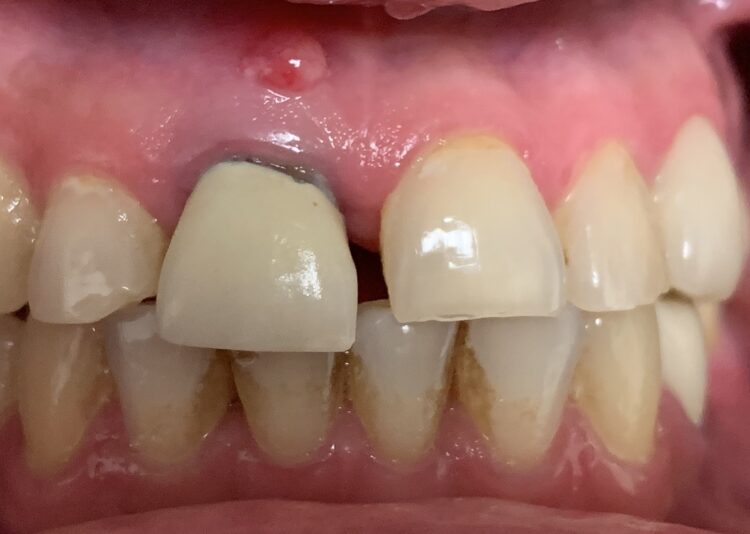

• This was a tough case with a large through-and-through defect on an upper central incisor. After the area was throughly cleansed I grafted using mineralized cortical particulate with CGF/PRF protocols. A thick collegen resorbable membrane was secured with membrane stabilizing sutures and primary closure achieved with a nonresorbable PTFE…

Read more